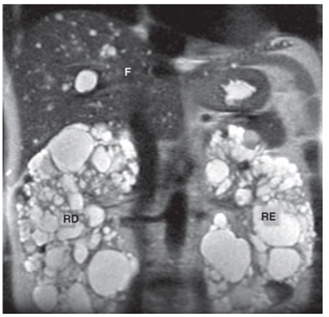

Observe a imagem a seguir.

A RM mostrada acima mostra o seguinte plano e a seguinte provável doença: